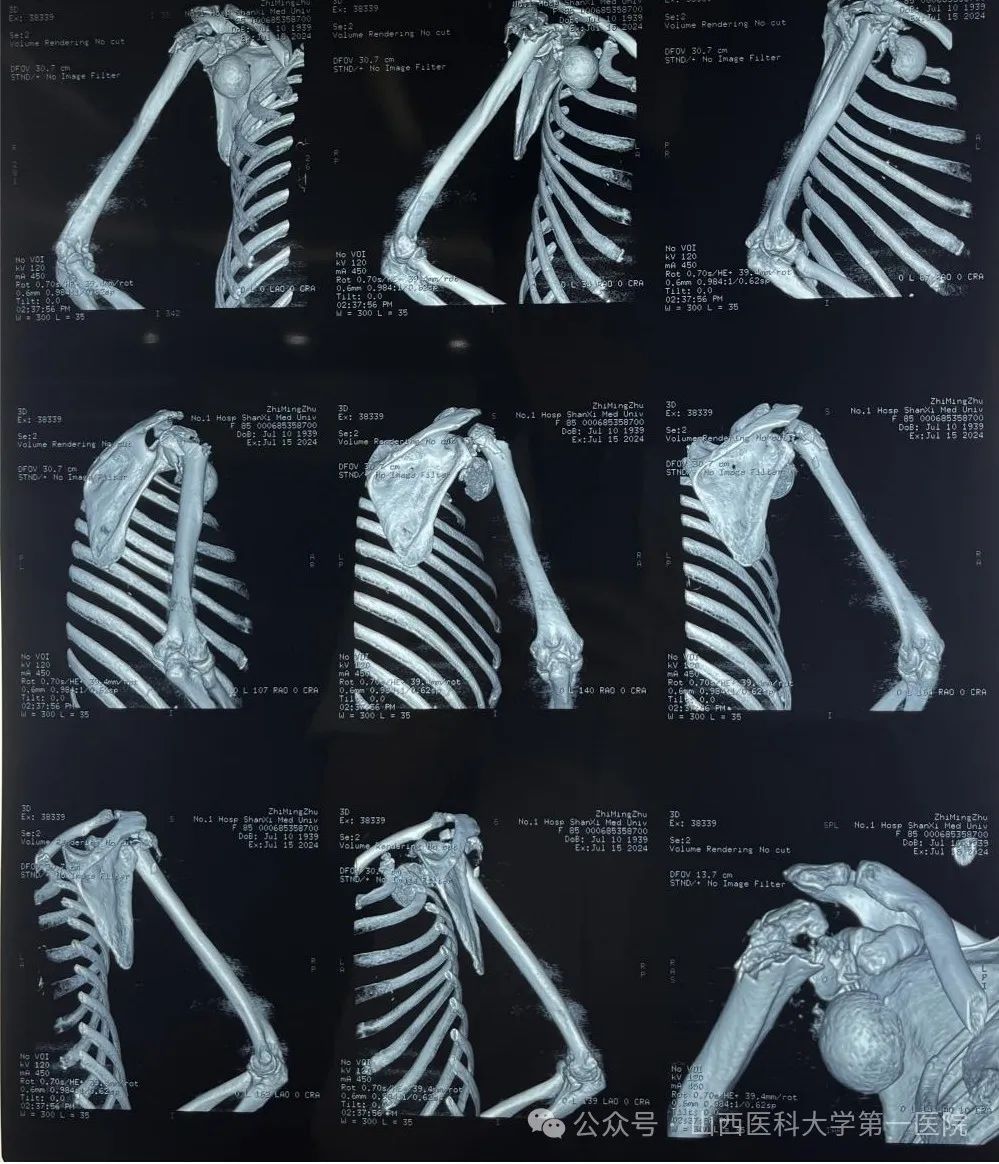

患者因摔倒致右肩、左腕部、右髋部疼痛伴活动受限3日余就诊于山医大一院骨科,入院诊断为:右肱骨近端粉碎骨折合并右肩关节脱位;左桡骨远端、腕骨、尺骨骨折;骨盆骨折。多处骨折尤以肩关节最为严重,术前影像学资料显示患者右侧肱骨近端粉碎骨折,肱骨头完全脱位卡在肩胛盂下方。

术前影像学检查结果